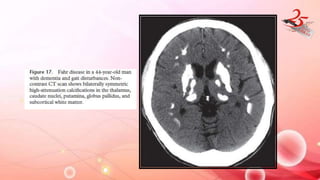

FAHR DISEASE

• Bilateral striopallidodentate calcinosis

• B/L symmetric deposition of Ca and other minerals in BG ,Thalamus

, Dentate nuclei and centrum semiovale in absence of

HYPOPARATHYROIDISM.

• CLINICAL FEATURES : Headache , vertigo , movt disorders , syncope ,

seizures , coma, dementia , parkinsonism , chorea, dystonia etc.

IMAGING FINDINGS:

• MRI/CT : B/l symmetric dense calcifications in BG , dentate nuclei ,

thalamus , subcortical white matter .